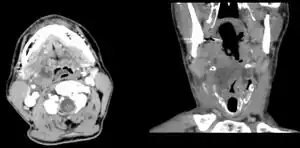

Diagnosis is usually based on the symptoms.[1] Medical imaging may be done to rule out complications.[1] Medical imaging may include CT scan, MRI, or ultrasound is also useful in diagnosis.[1]

-

Peritonsillar abscess on the person's right as seen on CT imaging -

Peritonsillar abscess